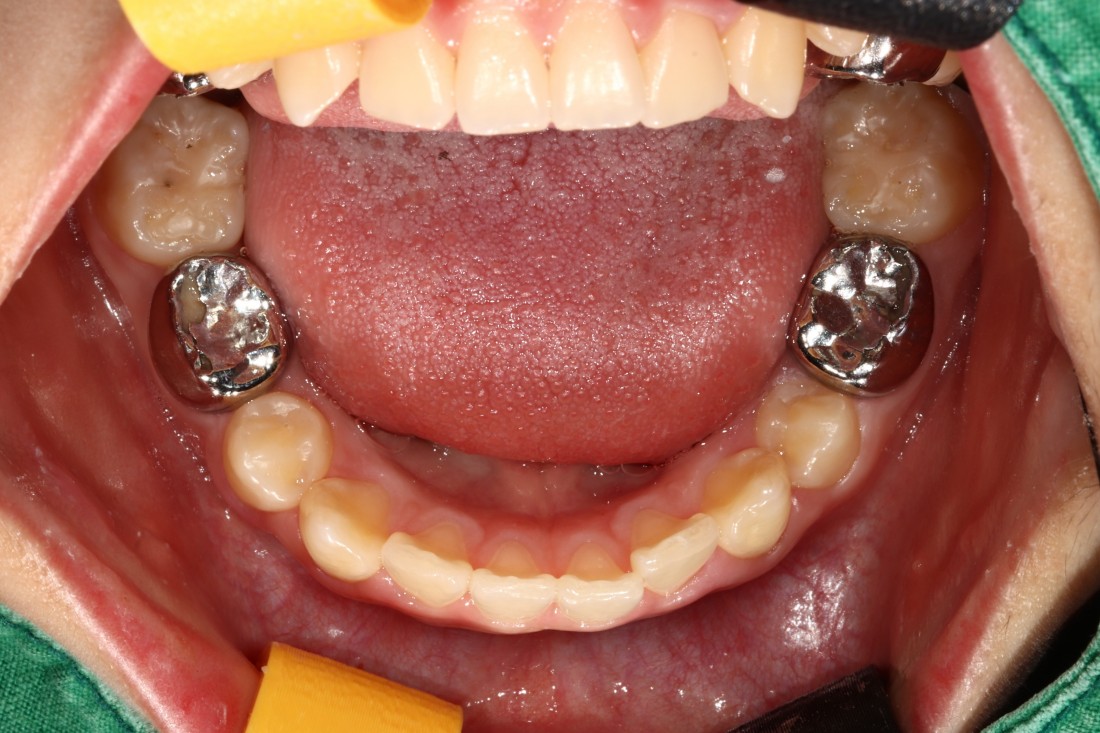

광주 덧니교정 치과는

대표원장인 제가 직접

다양한 교정 전/후 케이스를

공유하고 있습니다.

다양한 각도에서 촬영한

교정 전/후 사진을 직접 확인할 수 있어

광주 덧니교정 치과의

실력있는 진료를 증명하고 있습니다.

발치를 진행한 덧니교정이나

비발치 덧니교정 모두

다양한 케이스를 보유하고 있기 때문에

나의 구강구조와 비교해보면서

성공적인 교정치료 결과를

기대해보실 수 있습니다.